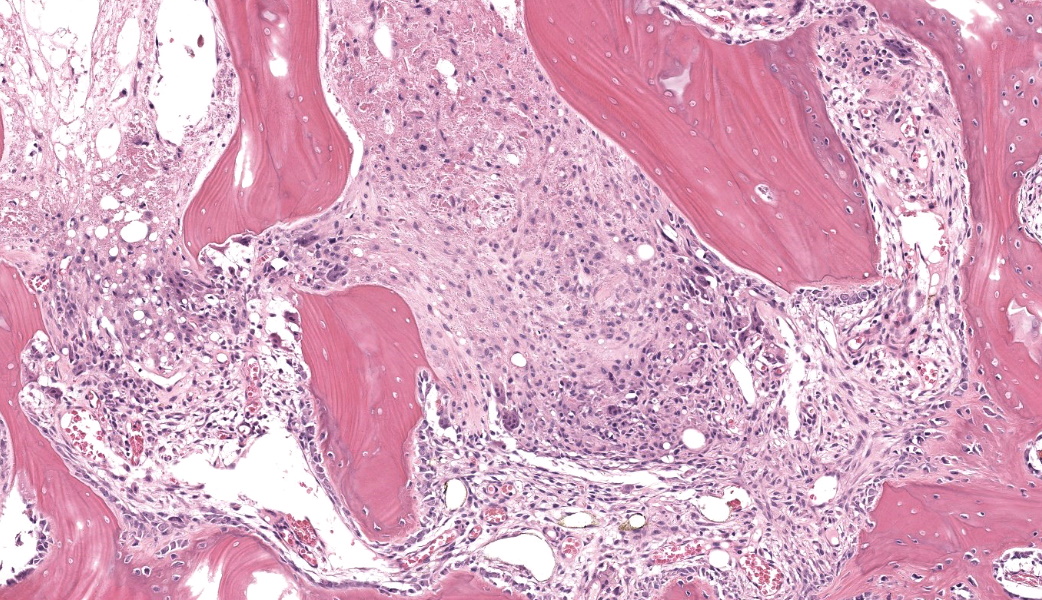

Femoral head: Affecting approximately 30-50% of the epiphysis from the subchondral aspect of the articular cartilage to the physis, there is a focally extensive area of osteonecrosis characterized by bony trabeculae which are irregular and brightly eosinophilic with loss of differential staining. There is loss of both osteocytes within lacunae and osteoblasts lining trabeculae in this region. Along the margins of the necrotic area, multiple bone trabeculae are fragmented and/or have scalloped margins with osteoclasts in Howship’s lacunae (osteolysis). The intertrabecular spaces within and at the periphery of the necrotic area contain variably amounts of amorphous eosinophilic matrix (fibrin), occasional neutrophils and macrophages and/or loosely arranged myxomatous to collagenous matrix with variable numbers of plump spindle cells and capillaries (fibroplasia). Occasionally, there are also finer, irregular trabeculae of paler staining or partially mineralized bone (woven bone). Adjacent viable trabeculae are lined by numerous active osteoblasts (remodeling) and are sometimes laced with wavy basophilic lines (resting / resorption lines). The articular cartilage is fragmented (likely artefact).Contributor's Morphologic Diagnoses:

The contributor of this case gives an excellent overview of this condition.Most of conference discussion was centered on pathogenesis and key histologic features of this condition. This disease can be, as stated by the contributor, either hereditary or secondary to trauma or other ischemic event.1,3,4,5,6 The hereditary form is most often seen in young, small breed dogs, such as terriers, dachshunds, pugs, Chihuahuas, and toy poodles. When looking at this case, there are a few histologic clues that can assist in determining the age of this animal, which can help with reaching the correct diagnosis. These include the presence of discontinuous physeal cartilage and the horizontal orientation of the bony spicules deep to the physis. In dogs, physes typically close around 10 months of age. Physis closure in Legg-Calves-Perthes disease (LCPD) is typically delayed secondary to ischemia of the physeal cartilage and the subchondral bone, which can result in a malformed or improperly angled femoral head.1 Additionally, in young animals, the bony spicules that extend into the metaphysis from the developing stages of the growth plate are oriented vertically (perpendicular) to the growth plate to facilitate the elongation of the bone. In older animals that have closed physes, the bone below the growth plate becomes oriented horizontally (parallel) to the growth plate, effectively “capping” it to facilitate closure of the physes. In this case, the bone has become horizontally oriented below the growth plate, indicating that this animal should have closed physes at this stage, but the presence of and discontinuity of the lingering growth plate indicate that this young animal is likely experiencing delayed physeal closure.

There are three recognized grades of LCPD and include: Grade 1, defined as necrosis of bone with empty lacunae, lack of viable bone marrow, and normal articular chondrocytes.

Grade II, characterized by cracks in the articular cartilage, subchondral bone collapse, and flattening of the femoral head with re-vascularization coming in from the periphery of the epiphysis +/- granulation tissue development; and Grade III, in which the articular cartilage is highly deformed with folds and cracks and the femoral head loses its shape.1

In the early stages (Grade I) of LCPD, the articular cartilage is spared because of its avascular nature.1,3,5 The subchondral bone, however, will become necrotic, and there is frequently a characteristic “tideline” of hypereosinphilia between the unaffected articular cartilage and the affected subchondral bone.3,5 As the condition progresses, however, the joint is subjected to altered conductive forces from abnormal weight-bearing, which places excessive pressure upon the articular surface and ultimately results in articular cartilage loss.1,5 This results in both the flattening of the femoral head from mechanical collapse and in asymmetrical growth between the affected limb and unaffected limb, as this disease is usually unilateral.5 Additionally, secondary to the altered conductive forces through the joint, new woven bone begins proliferating in an attempt to re-stabilize the bone and adjust for the altered force conduction.1 This woven bone is usually seen flanking either side of an area of lamellar bone to create a “sandwich” effect.